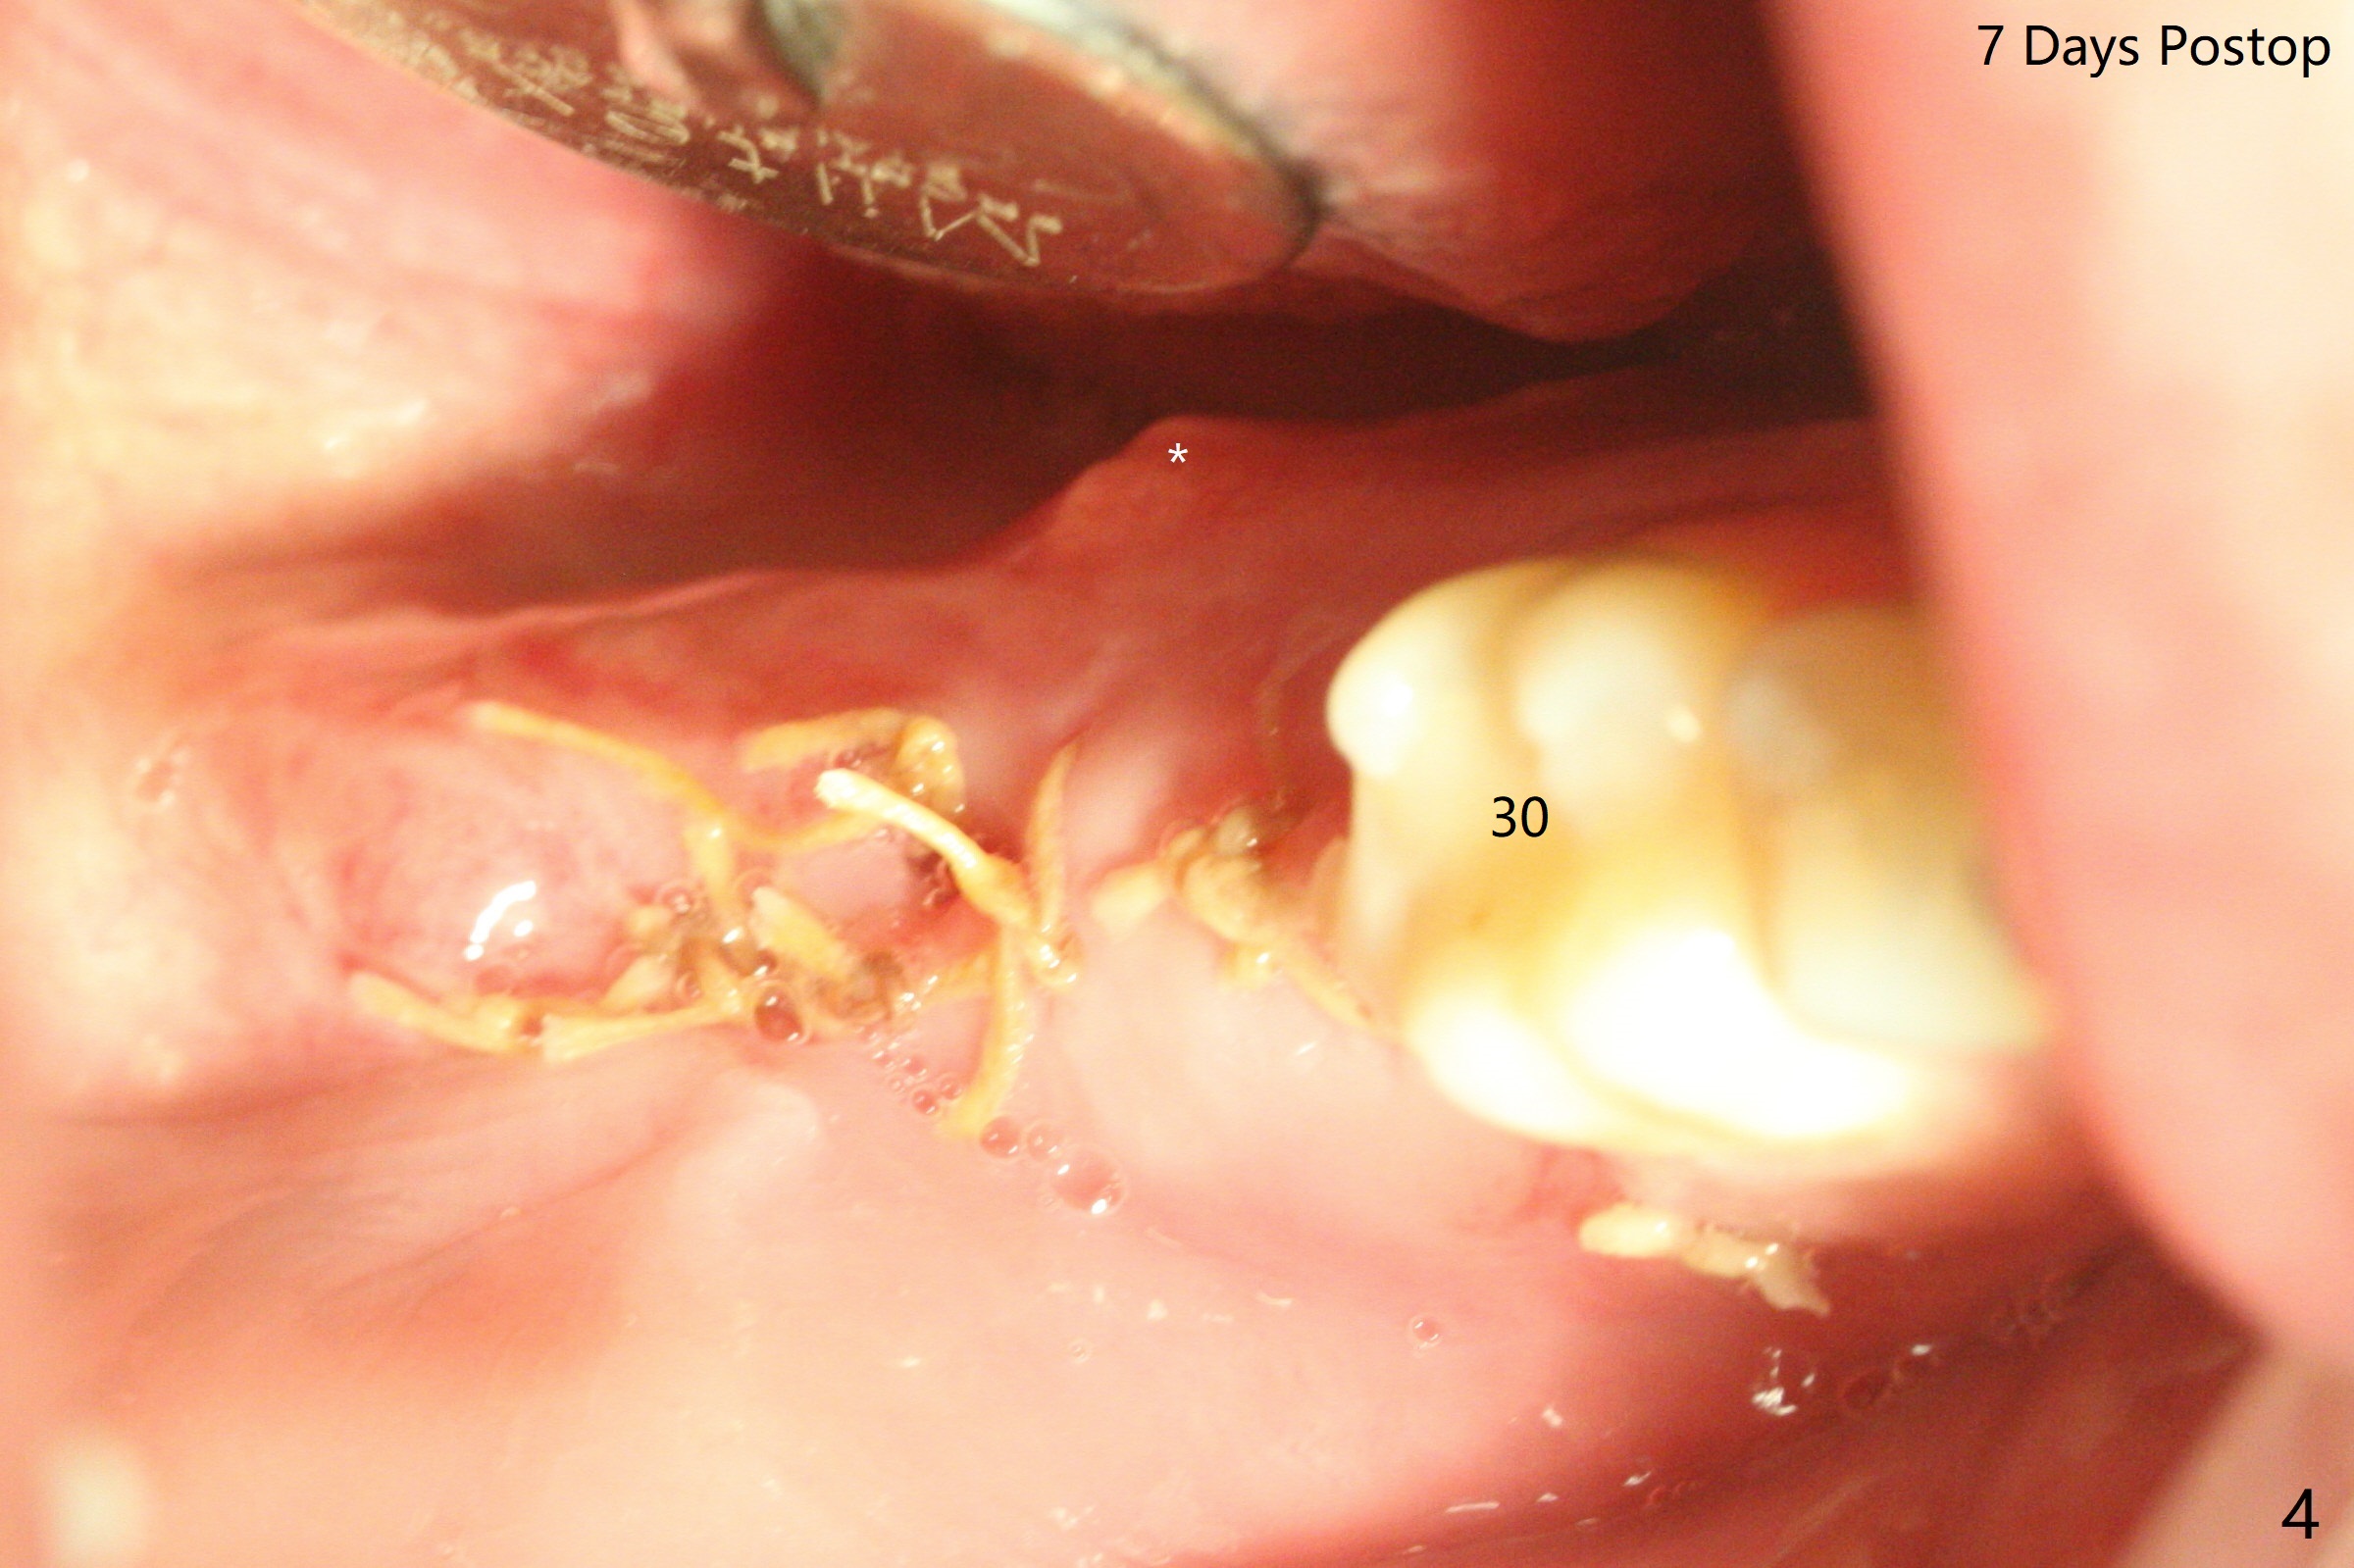

A 26-year-old man returns for #17,32 extraction 5.5 months post #1,16 one (Fig.1,2). In fact the crown/abutment at #31 is loose and removed, which makes easy for access, debridement with Titanium brush and bone graft (Fig.2 arrowheads, Ossogen). Osteogen plug is placed in the extraction sockets. The patient has limited mouth opening. Hemorrhage in #17 socket is controlled apparently with the plug following incomplete removal of granulation tissue. A piece of 12x12 mm Amnion-Chorion Membrane seems small for bone graft coverage. Cytoplast is added, followed by PGA suture. The former may keep the bone graft in place in case the wound dehisces. In fact the implant was not placed deep enough. It should have been removed. Although the wounds at #31/32 and 17 heal 7 days postop (Fig.3,5), the Cytoplast is visible immediately underneath the lingual gingiva at #31 (Fig.4 * (bulging)). The patient returns for Cytoplast (Fig.6 (occlusal view) *) removal 5 weeks postop. The procedure is done smoothly.